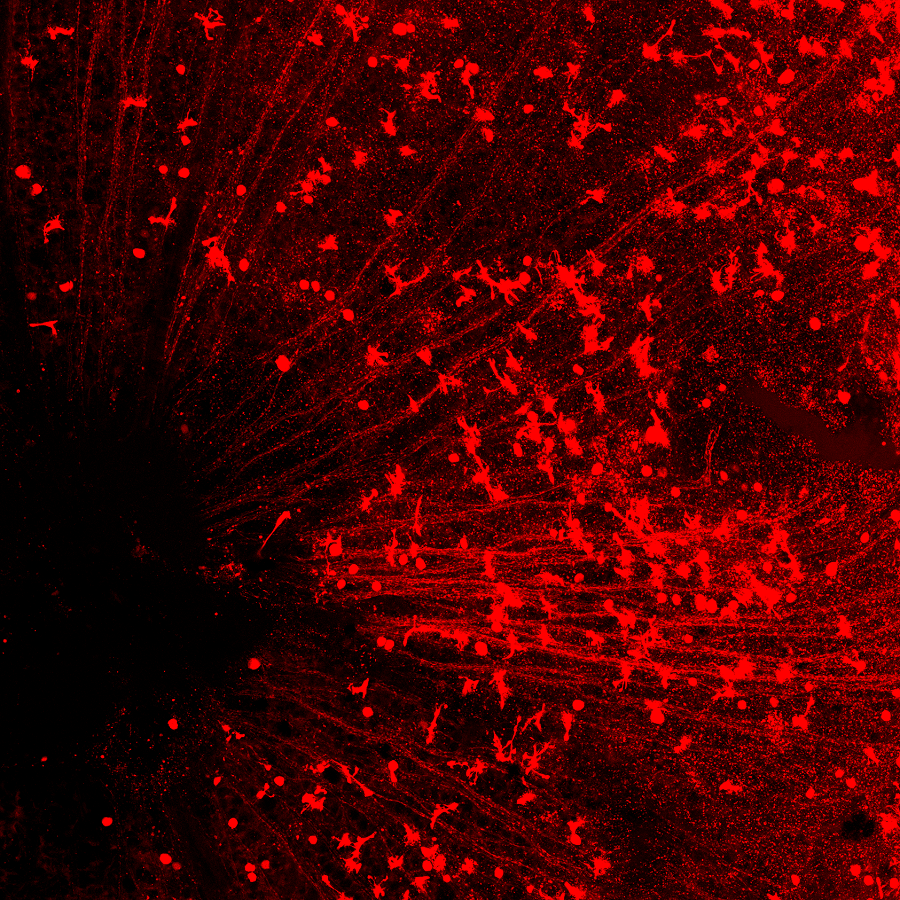

图注:(上)CasRx通过靶向的降解Ptbp1 mRNA从而实现Ptbp1基因表达的下调。(中)视网膜下注射AAV-GFAP-CasRx-Ptbp1可以特异性的将视网膜穆勒胶质细胞转分化为视神经节细胞,转分化而来视神经节细胞可以和正确的脑区建立功能性的联系,并且提高永久性视力损伤模型小鼠的视力。(下)在纹状体中注射AAV-GFAP-CasRx-Ptbp1可以特异性的将星形胶质细胞转分化为多巴胺神经元,从而基本消除了帕金森疾病模型小鼠的运动症状。

在小鼠的视网膜上,红色圆形的细胞是再生出的视神经节细胞,可以看到一条一条的红线汇集到眼睛中间的视盘(左下黑洞区域),这是再生出的视神经节细胞发出的轴突,它们将通过视盘传到视神经,然后再到大脑?!?/p>